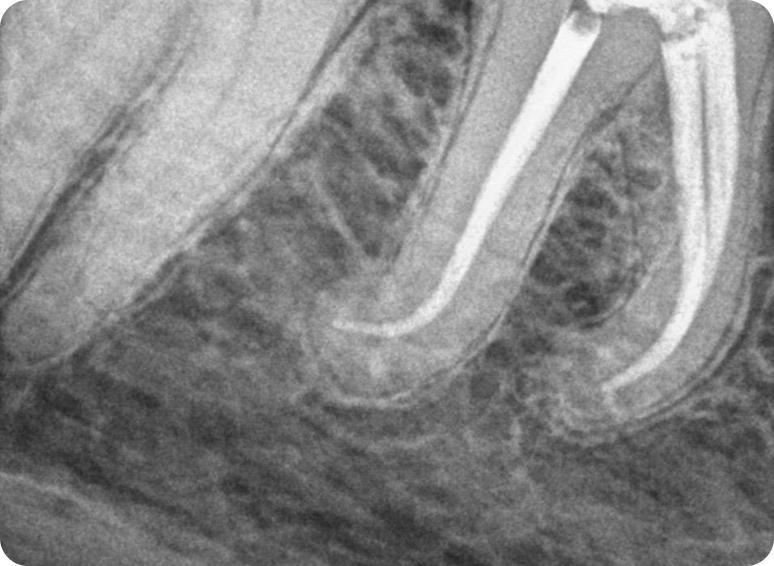

Una endodoncia (también conocida como tratamiento de conducto) es un procedimiento dental que se realiza para tratar problemas en el conducto radicular de un diente, específicamente cuando la pulpa dental (el tejido blando dentro del diente que contiene nervios y vasos sanguíneos) se ve afectada, generalmente por una caries profunda o una lesión.

La endodoncia implica la eliminación de la pulpa dañada, la limpieza y desinfección del conducto radicular, y luego el sellado del diente para evitar futuras infecciones. Este tratamiento puede salvar un diente que de otro modo necesitaría ser extraído.